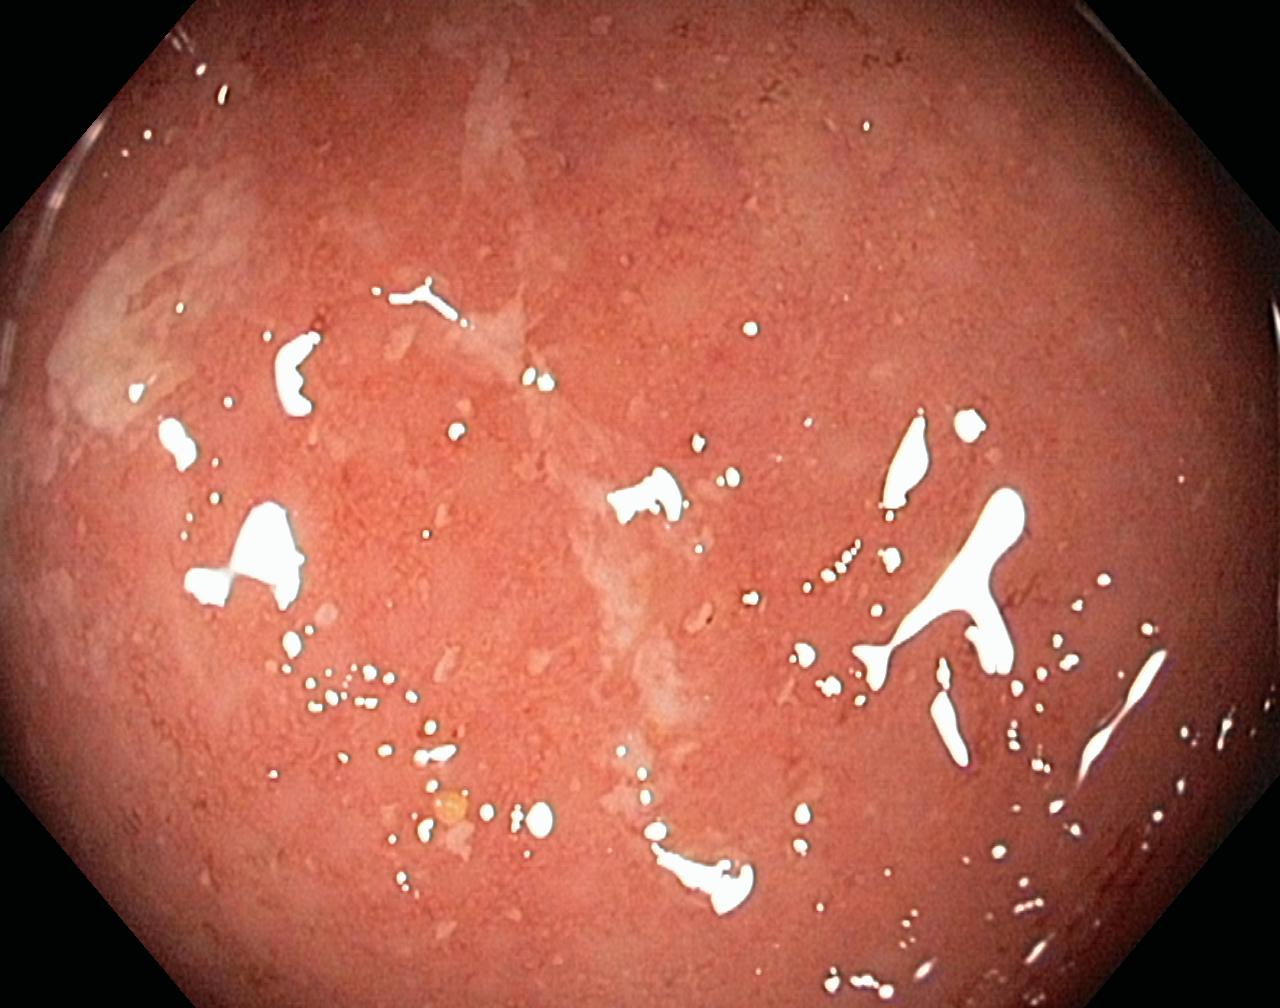

Obrazy endoskopowe

Zapalenie wrzodziejące...